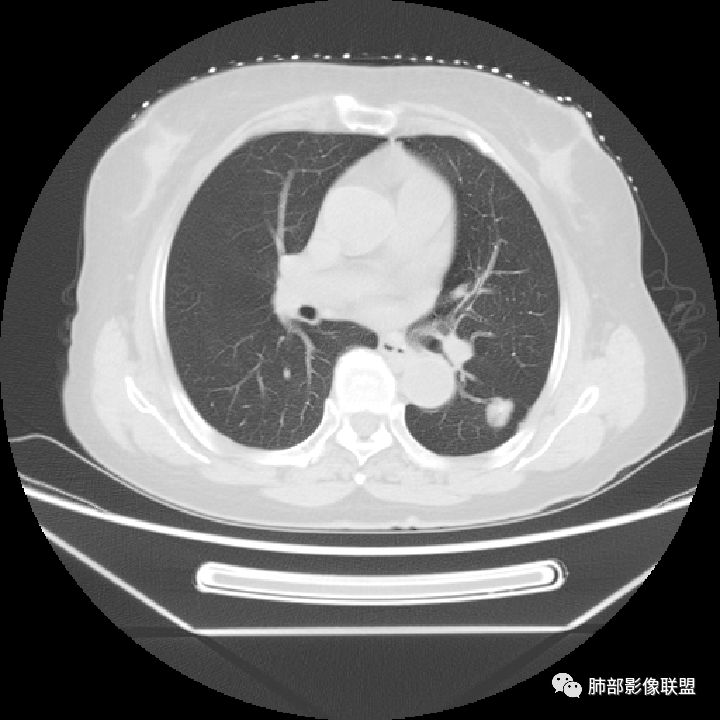

南边:你看看这个主体层面,大的一些层面,看看纵隔窗跟肺窗一对比,就发现病变不密实,似乎缩小了一大半,这就不正常了。

特别是在这种有瘢痕的基础上是吧,这个瘢痕很明显。南边:

以往有专家总结这个体积缩小超过一半的,一般会考虑炎性病变,为什么,它渗出为主的吧,但是我们后面的后来就发现这个老前辈总结出来的理论有很多东西,就不合适。磨玻璃影的边界,这个边界如何?清不清楚,这个很重要,如果边界是很模糊的,不用考虑那是炎症。那你像这种边界非常清楚的又不密实的,那种高度警惕恶性的。

1.肺部结节多钙化,常常是良性病灶的象征之一。如结核、错构瘤等。肺癌钙化不多见,如小细胞肺癌的钙化椒盐样分布,转移瘤结节常随机且多发等等。

2.本例肺结节内部钙化影规整而密实,既不同于错构瘤的“爆米花”或“桑葚”铺展,又有别于结核球的典型的同心圆样排布。

3.如我们无视这一钙化灶,结节影却似乎表现出另一副面孔,实性成份较多,边缘不规则,居然有磨玻璃有分叶、有异常供血、有棘状突起有胸膜牵拉等。病灶孤立,不像错构瘤静悄悄悬挂血管旁,亦未如结核球那样多卫星灶。

4.注意增强扫描,实性部分有较明显强化,这无论在结核球或是错构瘤都非常少见。

5.肺部钙化灶原本常见。肺组织并不会因为局部钙化灶的存在而豁免新生物。